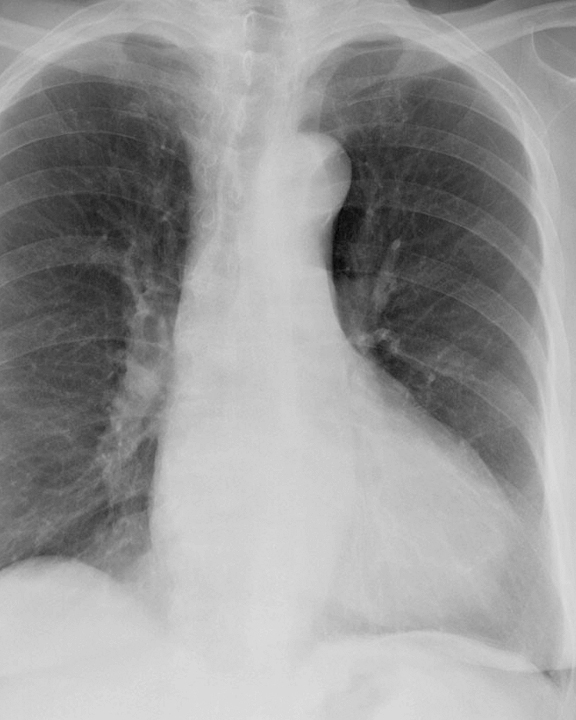

Case 8a Thymoma PA